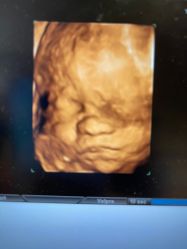

• -北京俪婴妇产医院(朝阳大悦城店)

相册

T9 上传于 22-07-02 | 报错